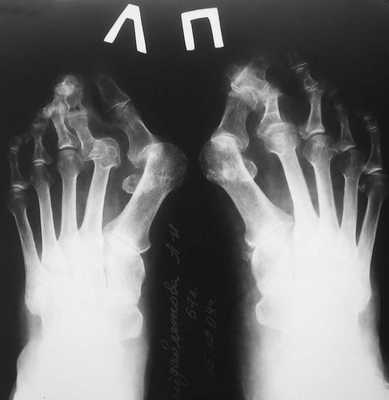

Классификация и стадии развития вальгусной деформации стопы

В зависимости от отдела деформации стопы — переднего или заднего, выделяют разные стадии заболеваний. Для определения стадии необходима рентгенограмма в двух проекциях и осмотр травматолога-ортопеда.

В деформации первого пальца выделяют три стадии на основании углов отклонения:

На основе данных рентгенографии выделяют три стадии заболевания. Степень деформации определяют на основании величины углов между первой и второй плюсневыми костями (межплюсневый угол) и отклонением большого пальца стопы.

3. Рентгенография. Обследование, выполненное в положении стоя и в двух проекциях, позволяет детализировать степень деформации и выбрать дальнейшую тактику лечения. Основное значение при анализе данных рентгенограмм играют следующие показатели:

- угол наклона дистальной суставной поверхности к оси первой плюсневой кости;

- угол, образованный осями первой и второй плюсневых костей;

- угол отклонения первого пальца от оси первой плюсневой кости;

- угол между осями ногтевой и основной фалангами первого пальца.